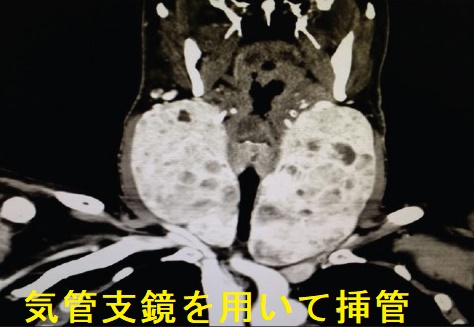

巨大甲状腺腫、甲状腺腫瘍や高度肥満による気管の圧迫・気道狭窄(最狭窄部1cm以下)のため、甲状腺切除手術における気道確保困難(挿管困難)が予測される場合、

- 気管支鏡を用いて挿管[Anesth Essays Res. 2015 MayAug;9(2):247-50.]

気道狭窄を伴い手術予定の巨大甲状腺腫患者が、間に合わず心肺停止した際、挿管困難が予想されたため、体外式膜型人工肺(extracorporeal membrane oxygenation:ECMO)下に緊急気管切開術をおこなった。それでも不十分なので、甲状腺腫減量術(いきなりここまでやる救命病棟すごいわ。救命病棟24時がノンフィクションに近いのが納得できます)を追加して救命できた報告があります。ECMOがあればこそ可能な処置とも言えます。(Jpn J Respir Care 2019;36:173-7.)